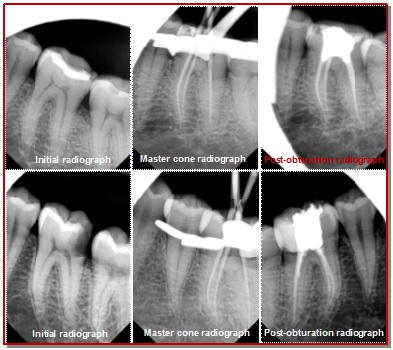

The purpose of this study was to compare the frequency and nature of pain between the vital inflamed (n=55) and non-vital (n=55) teeth that received single visit root canal treatment. The frequency and nature of pain were assessed as no pain, mild, moderate and severe pain on day 2 and day 7. The results showed that 76.4 and 85.5% participants felt no pain in vital inflamed teeth on day 2 and day 7, respectively. On the other hand, 63.6 and 74.5% participants felt no pain in non-vital teeth on day 2 and day 7, respectively. The remaining participants only felt mild to moderate pain. There were no significant difference between the two groups (p=0.435 on day 2 and p=0.371 on day 7). The results suggested that single visit root canal treatment is equally effective in both vital inflamed and non-vital teeth.